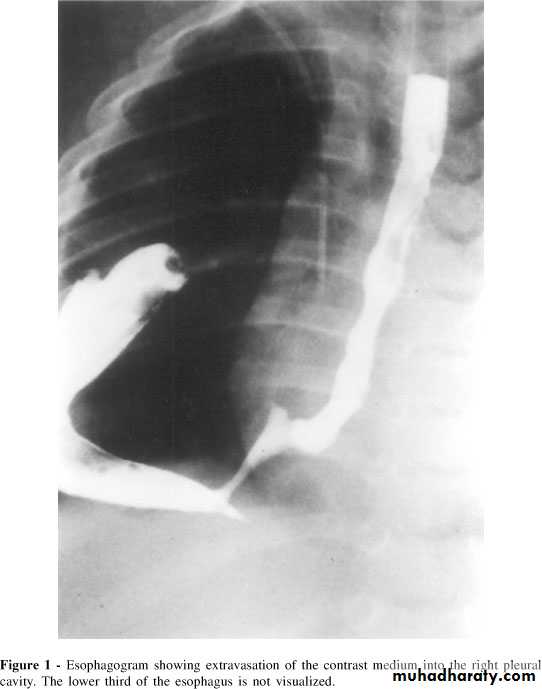

A 56 old woman present with four days history of breathlessness , cough and high fever. She give long history of indigestion and intermittent dysphagia to solids and liquids. On several occasions undigested food would be regurgitated back shortly after she had eaten. She would often wake at night with episodes of coughing and spluttering. There was no history of weight loss.

What type of complication the patient develop?